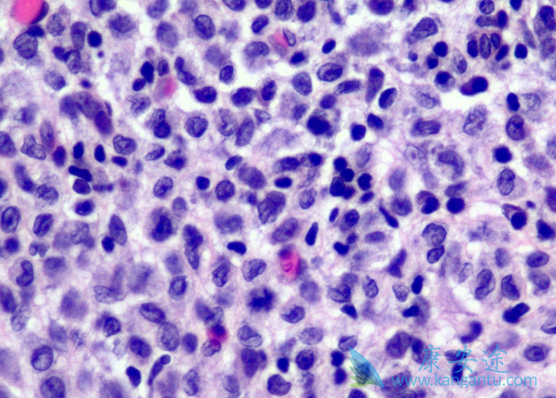

Erdheim-Chester 病(ECD)为一种罕见的非朗格罕组织细胞增生症,其中心脏与神经系统受累,与死亡率与发病率的显着增加相关。研究显示超过一半的 ECD 患者有 BRAFV600E 突变。威罗菲尼(Vemurafenib),是一种选择性低分子量 BRAF 激酶抑制剂,可以选择性抑制表达 BRAFV600E 突变蛋白的肿瘤细胞增殖,对转移性黑色素瘤(包括脑内转移)有效。

有研究显示,威罗菲尼对 3 名 ECD 伴 BRAF 突变患者高度有效。而本文报道了一例威罗菲尼有效治疗鞍上病变压缩视交叉神经导致视力减退的 ECD 患者。但这是一个单一的观察性研究,没有对照试验。在病人签署知情同意书后,开始使用威罗菲尼片治疗,具体剂量为 480mg(每天 2 次)。在第十天,两侧视力改善(左眼:0.7 升至 1.0;右眼:0.8 升至 1.0);双侧视野正常。通过 PET以及脑 MRI 对患者重新进行评估。PET 显示鞍上仅存有轻微残留;肺代谢亢进;MRI 检测显示肿瘤尺寸降低。最后在治疗期间没有副作用。